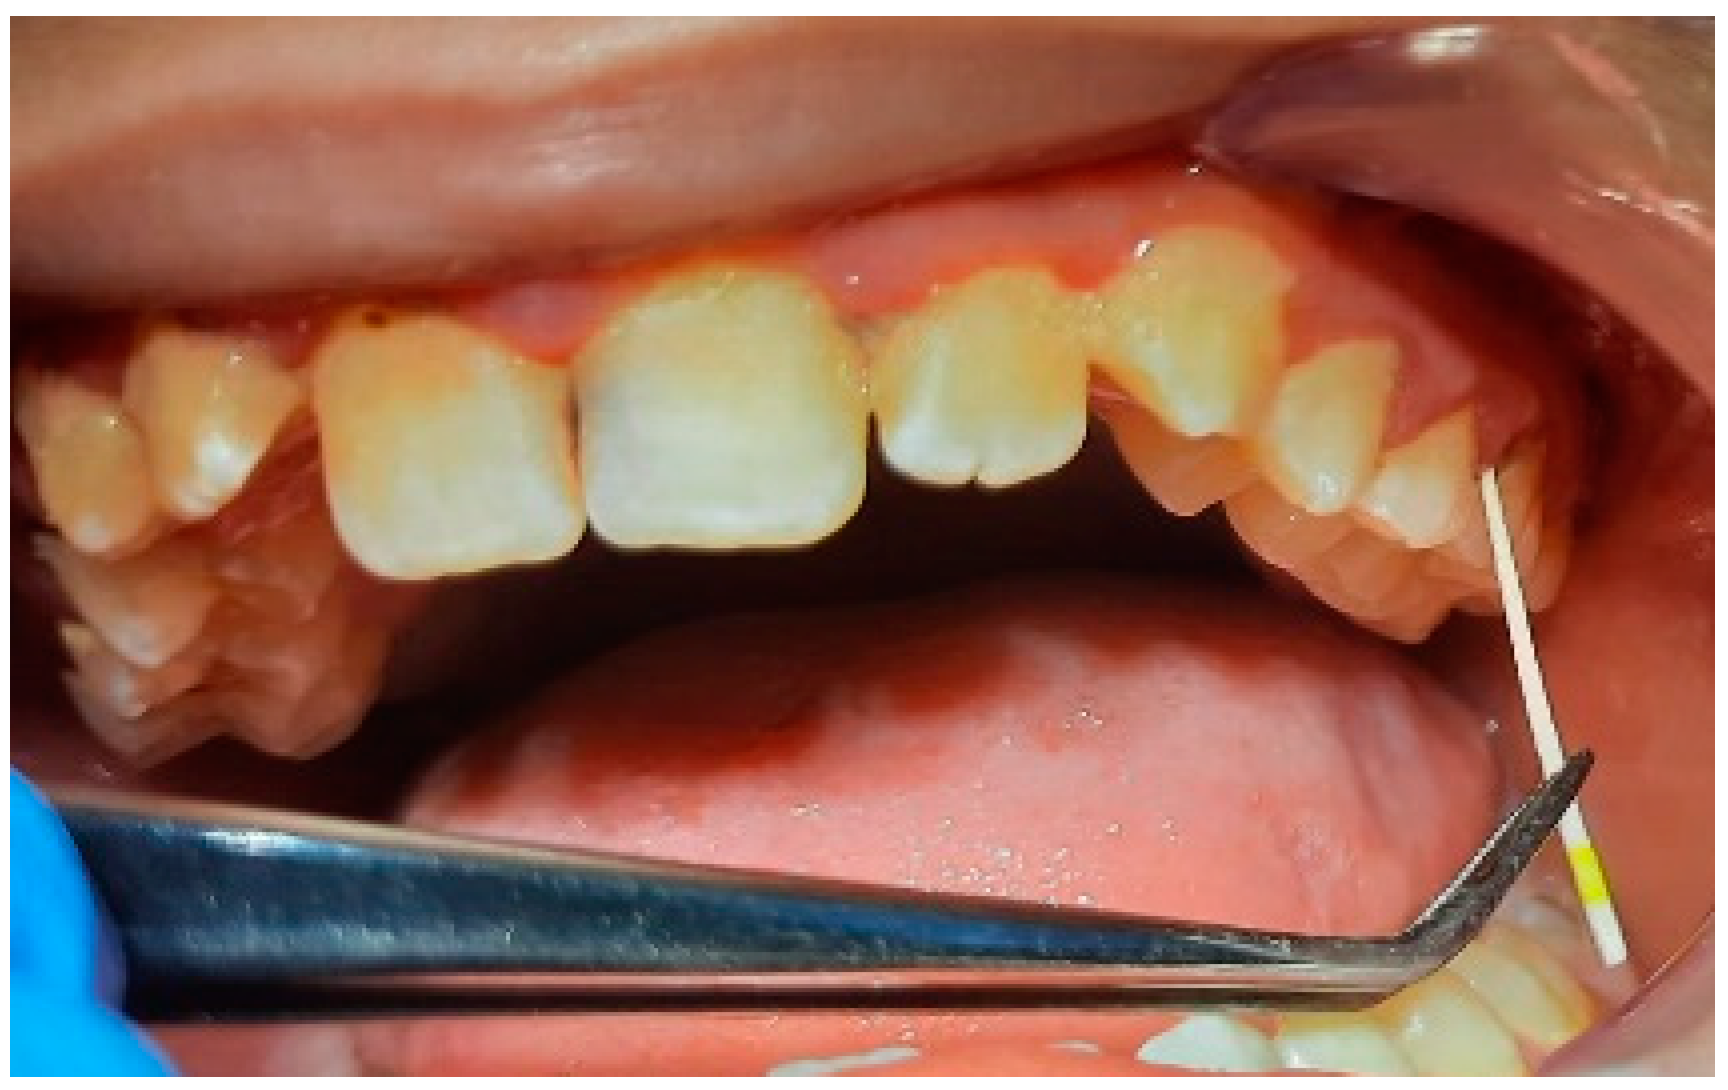

2.2. Clinical Examinations

3.2. Analysis of Clinical Data